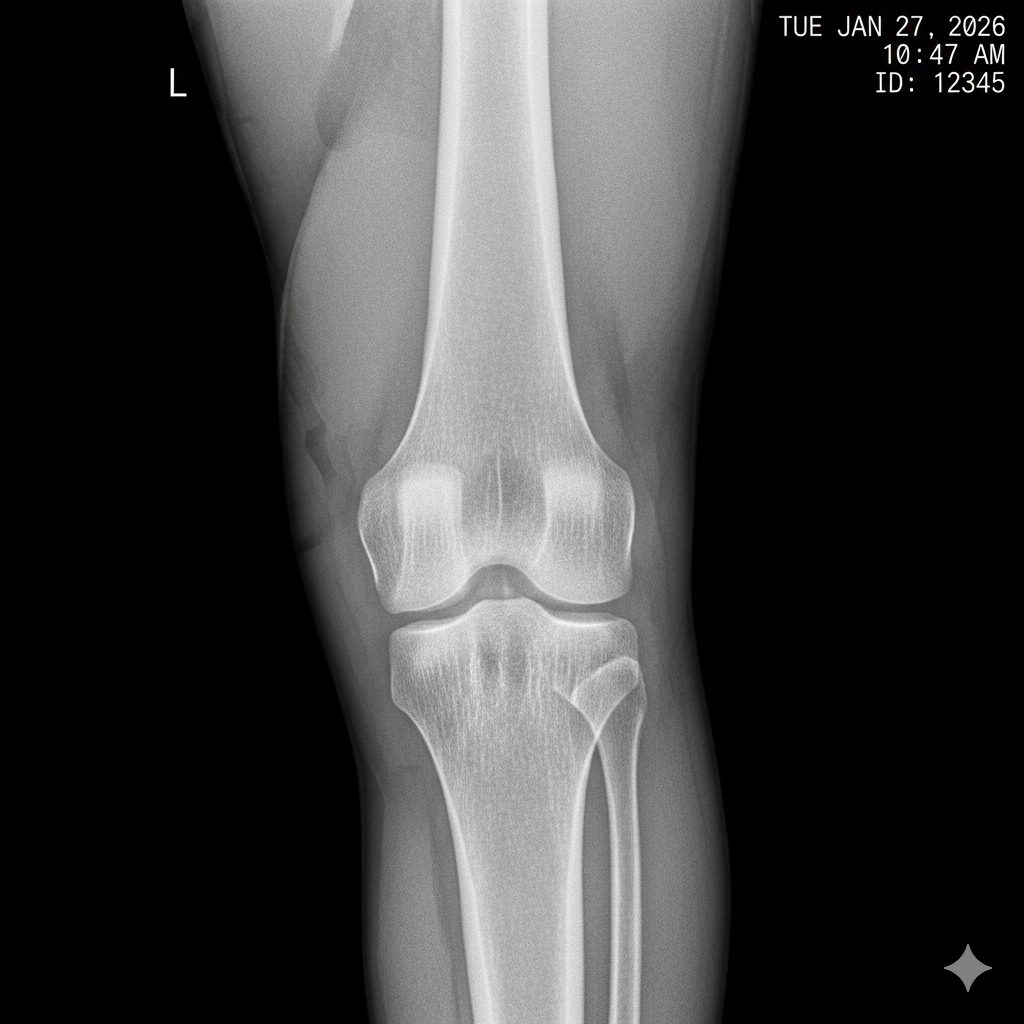

⑴「画像診断」という万能ではないツール

多くの人が「病院で検査をすれば、痛みの原因がテレビ画面のようにハッキリ映し出される」と信じています。しかし、ここには大きな落とし穴があります。レントゲンが最も得意とするのは「骨の形」を見ることです。骨折しているか、変形しているか、腫瘍がないか。これら「構造的な問題」を見つけるには非常に優れたツールです。

しかし、腰痛の多くは骨そのものが折れているわけではなく、筋肉、筋膜、靭帯、あるいは神経の伝達といった、「画像には写りにくい柔らかい組織」の問題で起きています。

つまり、レントゲンという「静止画」だけを見て、あなたの痛みのすべてを判断することは不可能なのです。